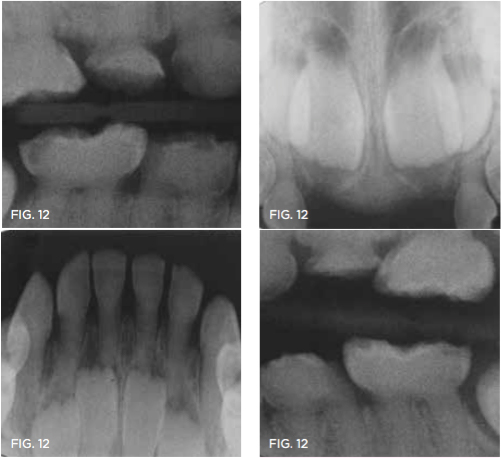

Case 4. At his first dentistry appointment, a 5-year-old with dentinogenesis imperfecta had large caries lesions on the distal of both mandibular primary first molars (Figure 12), along with smaller caries lesions on the distal of the maxillary right primary canine tooth and distal surface of the maxillary right first molar. The distal marginal ridge of the mandibular left second primary molar was fractured and subsequently trimmed smooth, but there was no caries detected in the exposed dentin. Stainless steel crown restoration of the primary first molars would have been difficult to accomplish because of the anatomical form of those teeth, the amount of wear/erosion of the maxillary first molars, and severity of carious destruction of the mandibular first molars. It was predicted that those teeth would be lost to extractions prior to their normal exfoliation time, therefore the goal was to preserve the teeth in place until eruption of the permanent molars to facilitate eventual space maintenance planning. It was thought that SDF could provide an immediate interim solution for caries control for this child, and after this was explained, the boy's father agreed to that treatment immediately at that visit. With cotton roll isolation, top layers of carious tooth substance were debrided from the mandibular first molars using a slow-speed round bur (Figure 13). No anesthetic injections were needed, and the patient related no discomfort. SDF was then painted on the caries lesions of the four teeth (Figure 14), followed by fluoride varnish application (Figure 15). The patient was seen several weeks later for renewed SDF application and dental prophylaxis (Figure 16 and Figure 17).

Fig 12. 5-year-old patient with dentinogenesis imperfecta had caries lesions of three primary  rst molars and the maxillary right canine tooth.

Fig 12